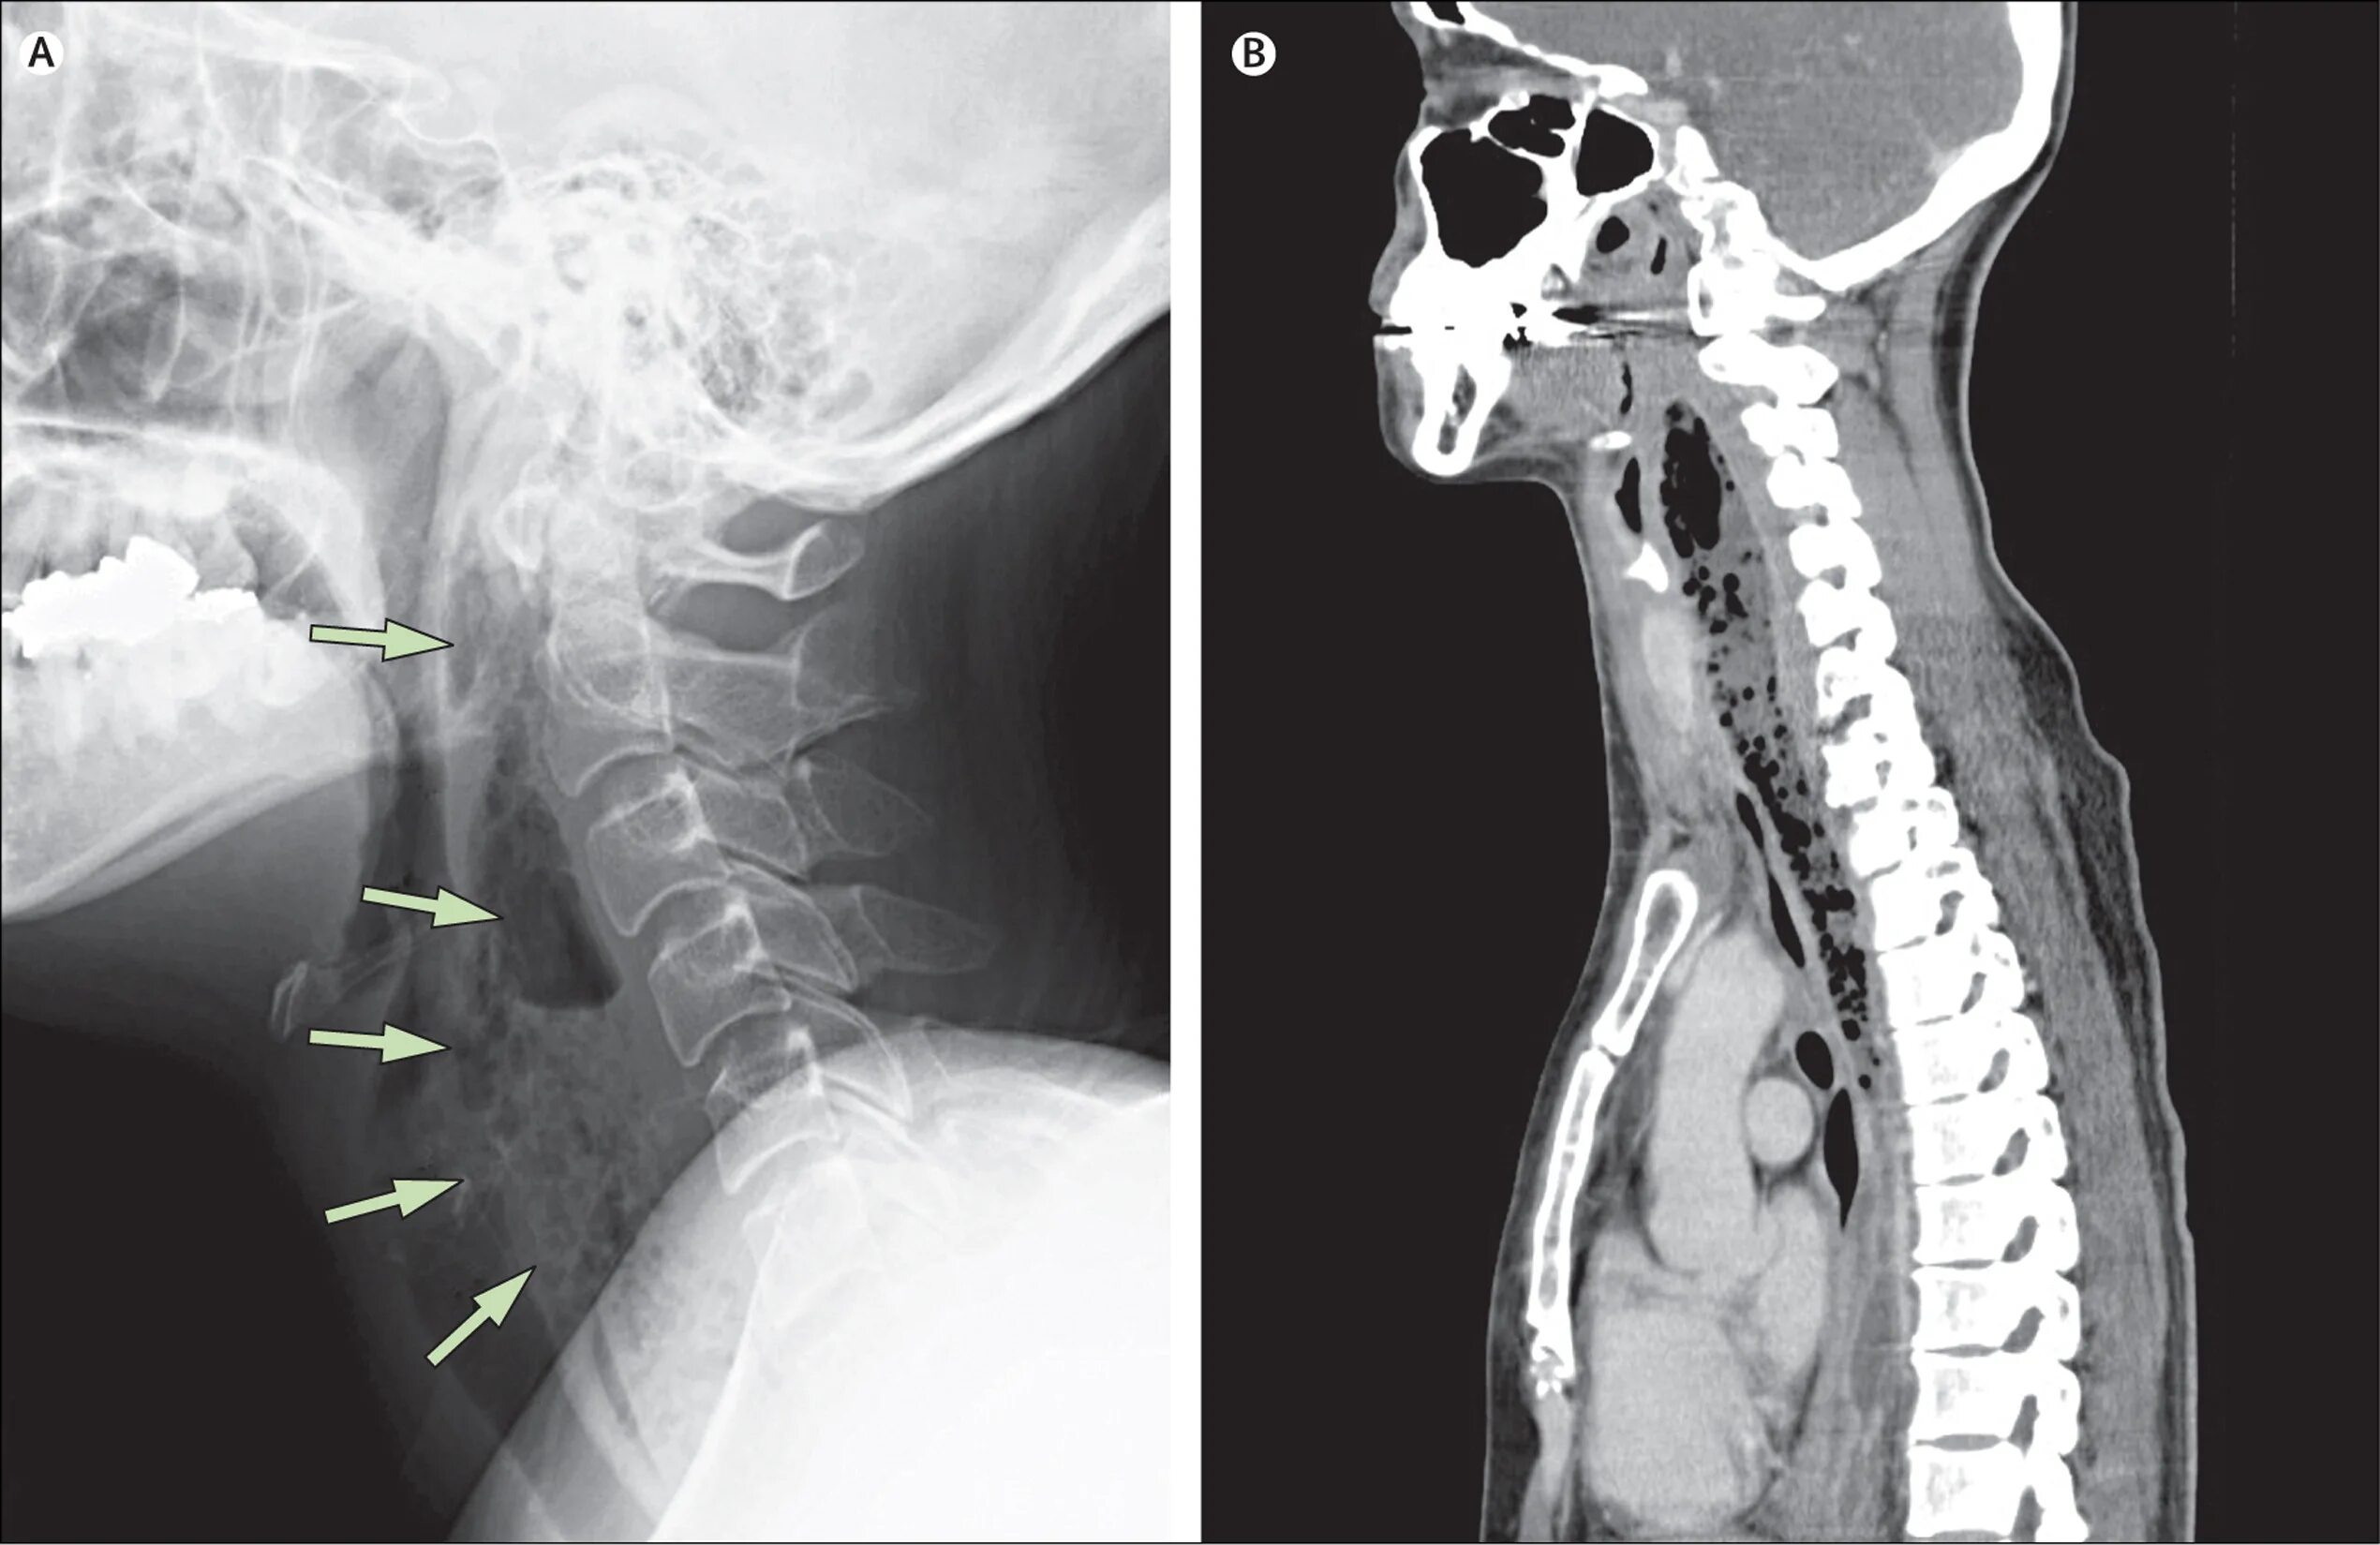

Пациентка 40